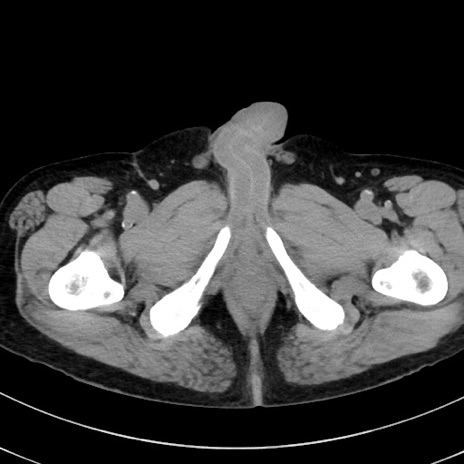

症例38(横断像)

【症例】70歳代 男性

【主訴】腹痛・嘔吐

【現病歴】昨晩より、嘔吐・腹痛あり。今朝になっても嘔吐あり。来院。

【既往歴】心臓バイパス手術、開腹胆摘、腸閉塞

【身体所見】BP 107/71mmHg、HR 116/min、腹部:平坦、軟、下腹部に軽度圧痛あり。反跳痛なし。

【データ】WBC 15100、CRP 0.32